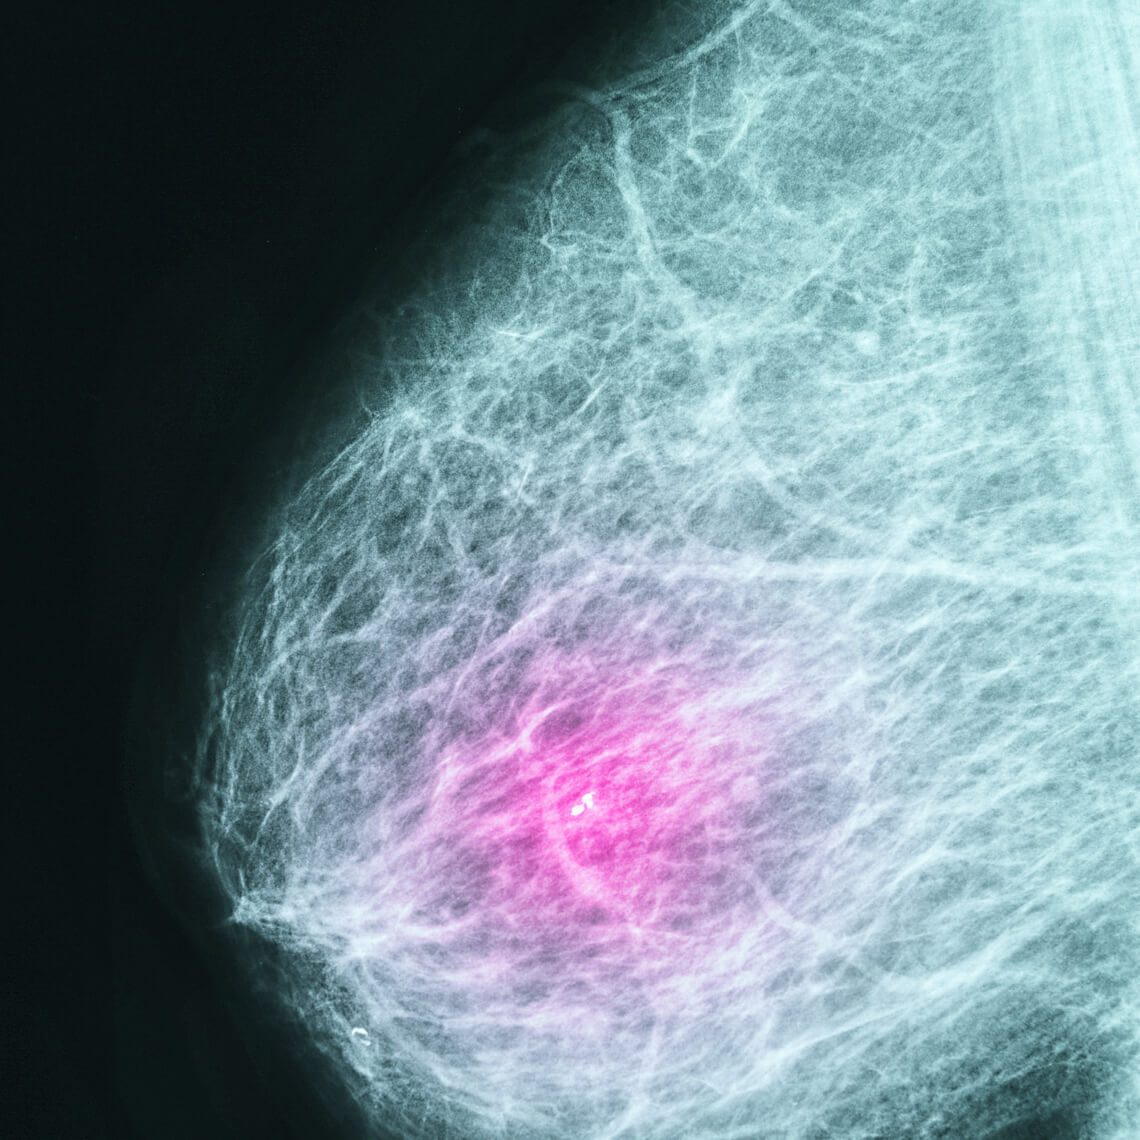

| Catching Breast Cancer In Women 40–49 Dr. Mara Schonberg (BIDMC) reports a conversation aid for PCPs counseling women about breast cancer screening. Help patients get the appropriate screening based on their personal risk...